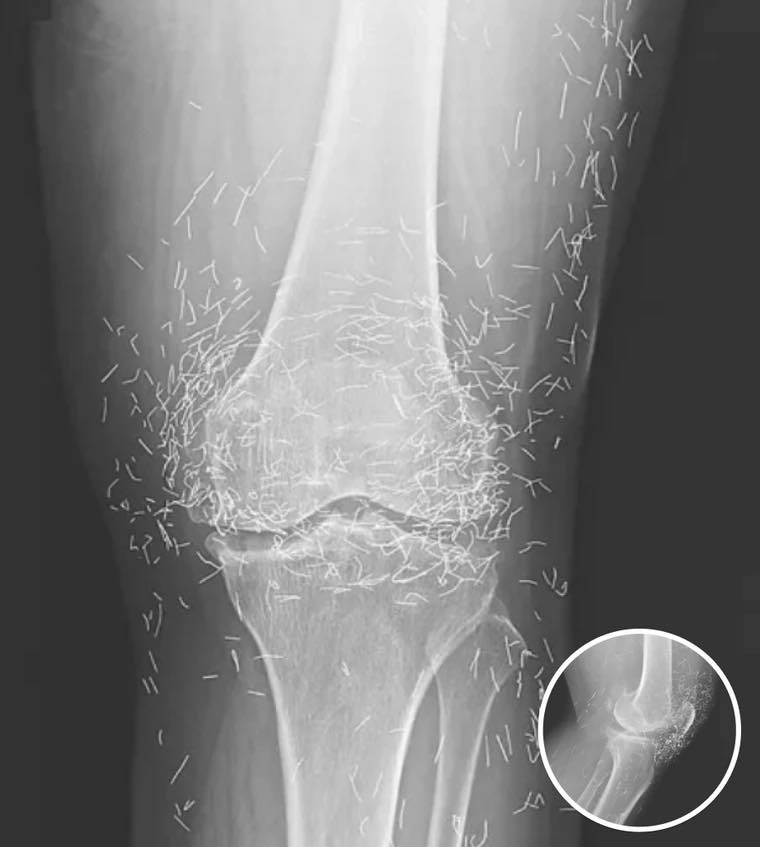

The X-ray images published in the New England Journal of Medicine showed dozens—possibly hundreds—of fine gold needles clustered around both knees. Some were deeply embedded in muscle tissue, while others rested just under the skin.

While gold is a non-reactive metal, the problem lies in the body’s defensive response. Over time, even inert materials can trigger inflammation as the immune system attempts to isolate the foreign objects. In severe cases, this leads to abscess formation or tissue hardening, both of which can worsen mobility and pain.

Another concern, Guermazi added, is that metallic fragments in the body can interfere with medical imaging. “Needles like these can distort X-rays or CT scans,” he said. “And MRIs are out of the question. The magnetic force could cause the metal to shift, potentially puncturing tissue or blood vessels. It’s extremely dangerous.”